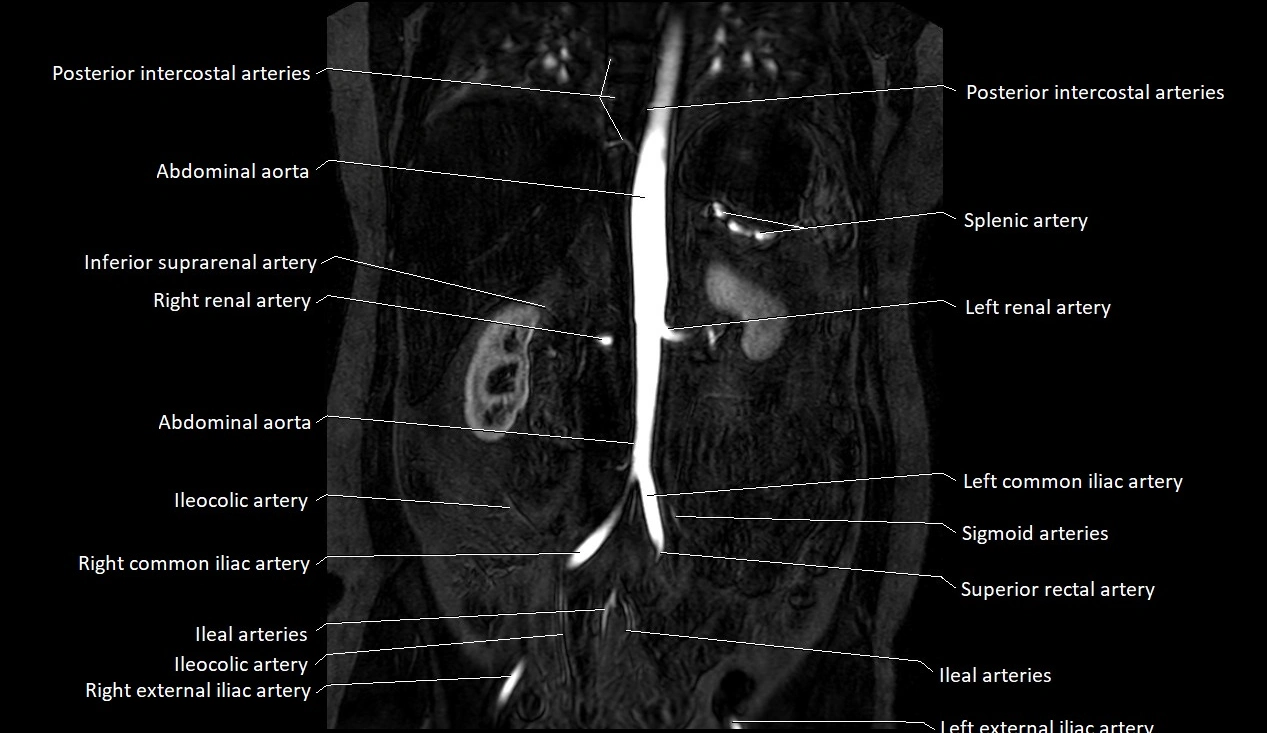

MRI images

image